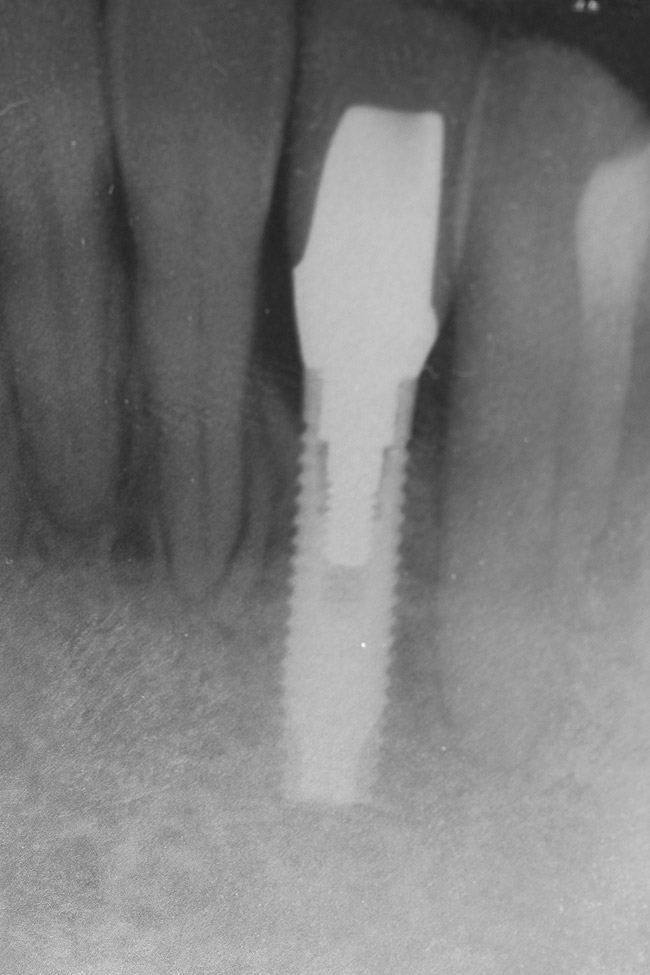

Figure 11  Radiograph showing developed implant site of tooth No. 23.

Figure 11